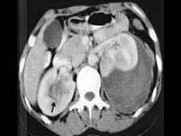

- 多项选择题女,26岁, 临床诊断为绒毛膜癌,行经腹子宫全切术后1月, CT检查如图所示,下列说法正确的是 ( )

A、左肾周可见低密度区,增强后无强化,其内有散在的片状稍高密度影

D、考虑为绒毛膜癌肾转移

E、合并有左肾周自发性血肿